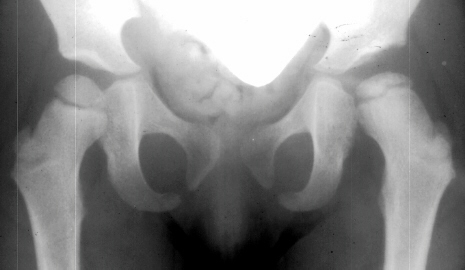

The progression of the hip is documented by x-rays taken at 1 year of age, 2 years of age, 3 years of

age, 5 years of age, 7 years of age, then at ten years of age, early closure of the lateral portion of proximal growth plate observed. Coxa valga was also observed.

The initial changes in the ossific center may follow exactly those seen in Group I, but in addition there is damage to the lateral part of the physis. The early roentgenographic signs indicating lateral physeal damage are: (1) lateral ossification, (2) lateral physeal irregularity and bridging, (3) lateral notching of the epiphysis, and (4) a lateral metaphyseal defect. The damage to the physis may remain dormant. By the age of ten years, however, valgus deformity of the head on the neck develops.( This type occurred in 35% of total AVN at AIDI.)